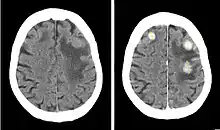

Iodinated contrast is a form of intravenous radiocontrast agent containing iodine, which enhances the visibility of vascular structures and organs during radiographic procedures. Some pathologies, such as cancer, have particularly improved visibility with iodinated contrast.